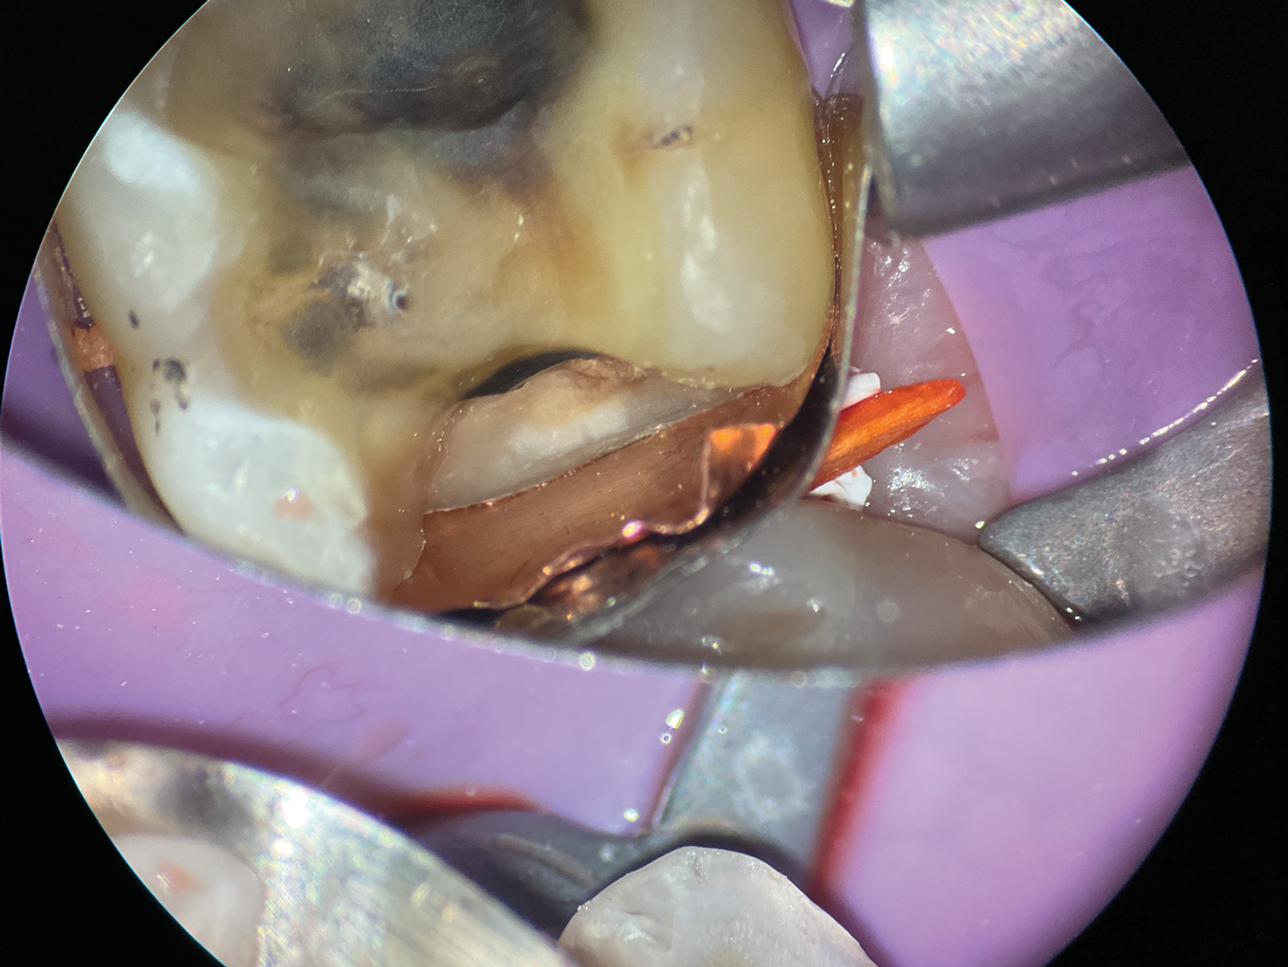

(10.) A close-up distolingual view of a mandibular molar after the removal of caries that extended to the bone level.

Figure 10

(11.) A Willems probe was used to determine that the depth of the margin was approximately 7 mm from the occlusal surface.

Figure 11

(12.) After subgingival placement of a Tofflemire matrix, despite using a wedge and adding additional support with polytetrafluoroethylene tape, fluid infiltration persists through the matrix and margin.

Figure 12